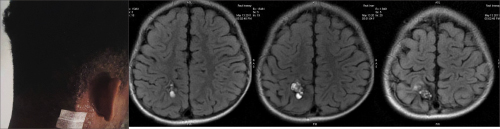

SEAN Kamati, a 26-year-old man from Windhoek, was diagnosed with a brainstem cavernoma in June this year.

Kamati said that it all started in the beginning of June this year, when he believed to be suffering an ear infection. “But then we discovered it was much more, like headaches and numbness. I consulted a doctor and he sent me for scans. I was told I had what you call a cavernoma, a vascular malformation on my brain stem and it needed to be removed,” Kamati said.

He was also told cavernomas are clusters of abnormal blood vessels mainly found in the brain and spinal cord. They are sometimes known as cavernous angiomas, cavernous hemangiomas or cerebral cavernous malformations.

The group further added that there are two possible options available for patients who are found to have cavernoma, and one is surgery. Kamati underwent a seven-hour operation, which took place at the Grootte Schuur Hospital in Cape Town, South Africa on 7 June and said that it went well and that the abnormal formation of blood vessels in his brainstem was successfully removed.